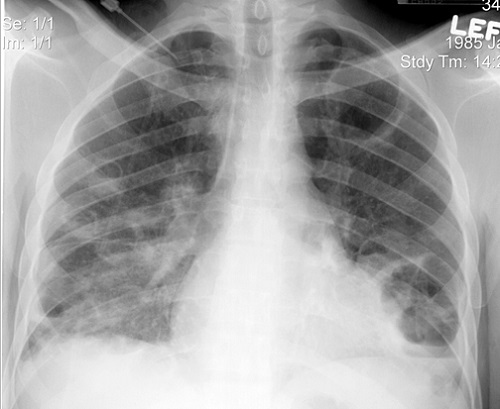

Chụp X-quang phổi thấy hình ảnh nhiều ổ viêm phổi dạng tròn, kích thước không đều, ở hai bên phổi, không đối xứng. Khám thấy rì rào phế nang giảm và nhiều ổ ran nổ.